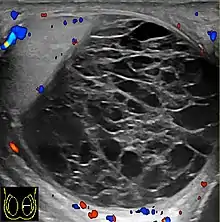

The US appearance of varicocele consists of multiple, hypoechoic, serpiginous, tubular like structures of varying sizes larger than 2 mm in diameter that is usually best visualized superior or lateral to the testis [Fig. 27a]. Color flow and duplex Doppler US optimized for low-flow velocities help confirm the venous flow pattern, with phasic variation and retrograde filling during a Valsalva's maneuver [Fig. 27b]. Intratesticular varicocele may appear as a vague hypoechoic area in the testis or mimics tubular ectasia. With color Doppler, this intratesticular hypoechoic area also showed reflux of vascular flow during Valsalva's maneuver [Fig. 28].